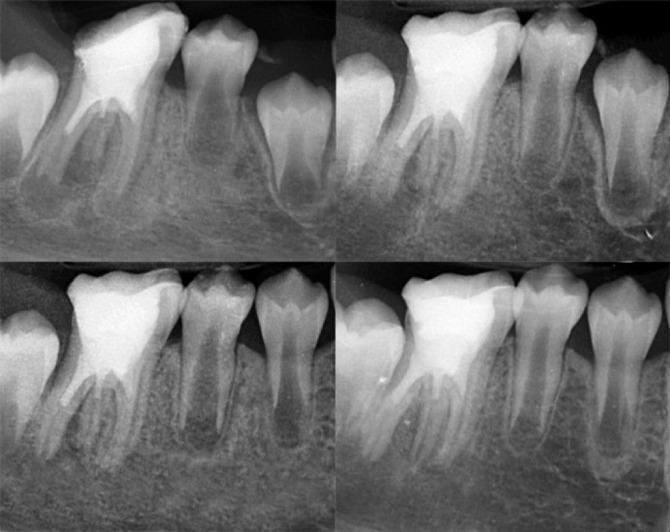

Regenerative endodontic procedures (REPs) have emerged as a biologically driven approach for managing immature teeth with necrotic pulp and open apices, providing an alternative to traditional apexification techniques. This case report describes the successful treatment of a three-rooted immature mandibular first molar with necrotic pulp and chronic apical periodontitis in a 9-year-old patient using REPs. The treatment followed the guidelines set by the American Association of Endodontists and utilized a two-visit protocol. Concentrated growth factor (CGF) was employed as a biological scaffold in the root canals, while calcium-enriched mixture (CEM) cement was used for the coronal seal. Radiographic evaluations conducted at 6, 12, and 15 months revealed progressive periapical healing, significant root elongation, increased thickness of the root walls, and partial apical closure. Clinically, the patient remained asymptomatic during all follow-ups. This case highlights the potential of CGF and CEM cement-enhanced REPs to promote continued root development and achieve predictable outcomes in immature teeth with necrotic pulps, offering a biologically based alternative to conventional apexification.

再生牙髓治疗程序(REPs)已成为一种以生物学为驱动的方法,用于处理牙髓坏死且根尖孔开放的未成熟牙齿,为传统根尖诱导成形技术提供了一种替代方案。本病例报告描述了一名9岁患者的下颌第一恒磨牙三根未成熟牙,患有牙髓坏死和慢性根尖周炎,采用REPs成功治疗的过程。治疗遵循美国牙髓病学家协会制定的指南,并采用了两次就诊方案。浓缩生长因子(CGF)被用作根管内的生物支架,而富钙混合物(CEM)水泥用于冠部封闭。在6个月、12个月和15个月时进行的影像学评估显示根尖周逐渐愈合、牙根显著伸长、根壁厚度增加以及根尖部分闭合。临床上,患者在所有随访期间均无症状。本病例突出了CGF和CEM水泥增强的REPs在促进未成熟牙髓坏死牙齿持续牙根发育并实现可预测结果方面的潜力,为传统根尖诱导成形提供了一种基于生物学的替代方法。